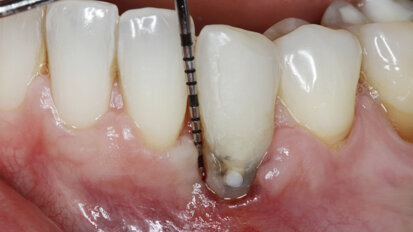

Management kosti a měkkých tkání při komplexní rekonstrukci jednoho zubu implantátem

Rekonstrukce jednoho frontálního zubu implantátem bývá pravděpodobně největší estetickou výzvou pro praktického zubního lékaře. Správné ...